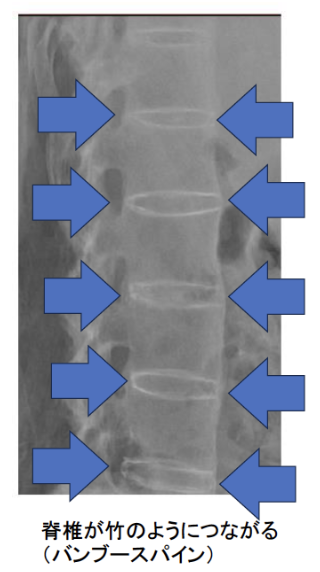

強直性脊椎炎は仙腸関節と脊椎に炎症を引き起こすことで、難治性の腰背部痛を発症します。また、進行すると仙腸関節がくっつく(強直)ことや、脊椎の靱帯が骨でつながる(バンブー(竹)スパイン(脊椎))ことで、背骨が動かしにくくなります。